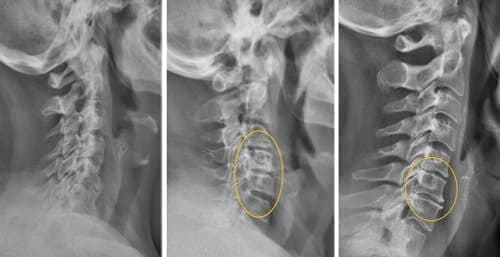

Mire estas fotografías. Esto es lo que les sucedió a todos los que ignoraron los síntomas. Hoy, estas personas están completamente sin esperanza, y muchos de ellos no tienen a quién acudir en busca de ayuda. ¿Realmente, quiere un destino así?

Hernia de disco intervertebral, compresión de los nervios, pérdida de sensibilidad y parálisis parcial de las piernas.

Todas las articulaciones están sujetas al desgaste; sin embargo, la ausencia de terminaciones nerviosas en la columna puede ocultar cambios catastróficos. La compresión del nervio ciático por una hernia es un proceso doloroso, que empieza con un dolor leve en la zona lumbar y se extiende a las piernas con hormigueo y entumecimiento, hasta llegar a un bloqueo completo. El daño progresivo conduce a la parálisis de las piernas, haciendo que recuperar el control sea prácticamente imposible.